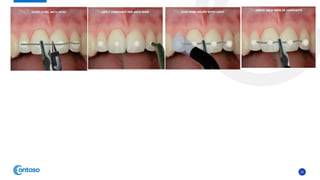

A, B, Clinical appearance of wire-composite splinting of maxillary and mandibular incisors;

C, D, Radiography was taken to ensure correct positioning of the teeth,

The splint was extended to the primary canines.